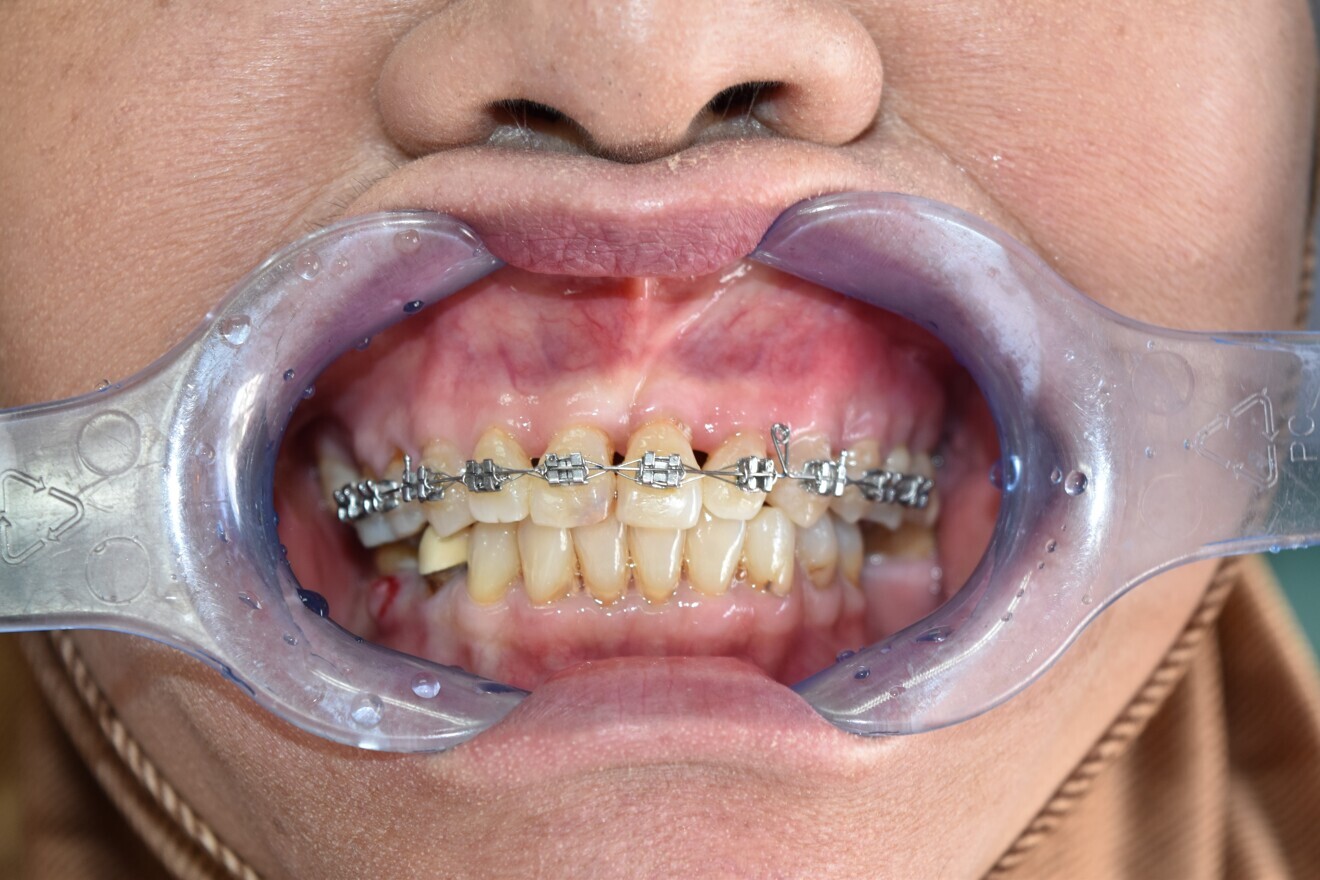

Fig. 12a: Lower arch bonded first to collapse in pursue of overjet and overbite.

Fig 12b:  Upper arch bonded once spaces in lower arch managed.